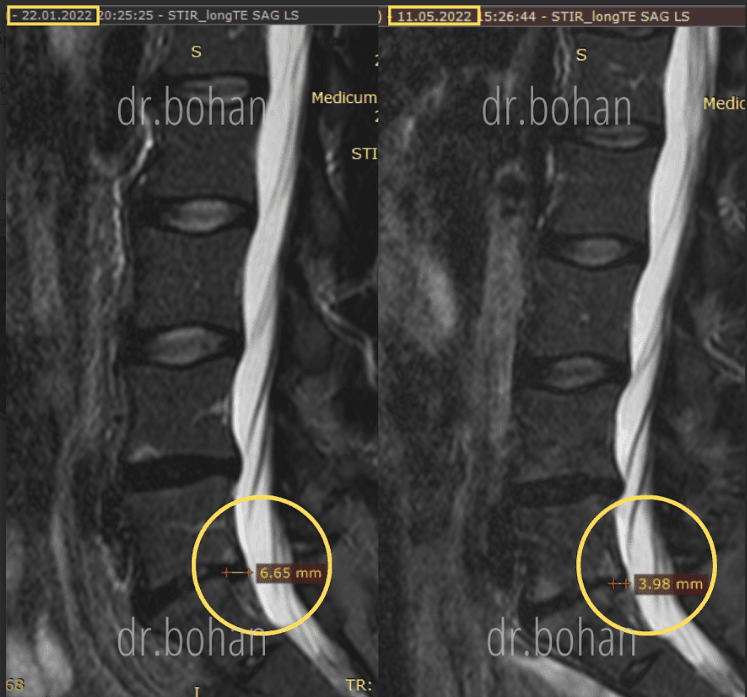

Метод лікування грижі шляхом стимуляції резорбції в Україні був впроваджений у 2020-2021 роках.  Алгоритм оцінки грижі на предмет резорбції, що використовується у клініках – є авторським, розроблений лікарем Боханом А.Ю.